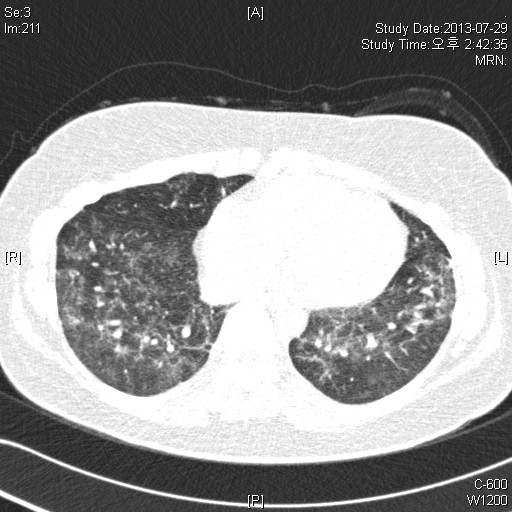

39¿©ÀÚ È¯ÀÚ·Î, Rt breast cancer Áø´ÜÇÏ¿¡ 2013³â 3¿ùºÎÅÍ Ç×¾Ï Ä¡·á ¹ÞÀº ȯÀÚ·Î,

dyspnea on exertion ¾ÇÈ­µÇ¾î È£Èí±â³»°ú ¹æ¹®ÇÔ.

CRP 0.68 mg/l, Procalcitonin<0.05 mg/dl

CBC: 6000-12.1-246k(neutrophil:71.8%, eosinophil 1.0%)

PFT: FVC/FEV1/Ratio: 2140(56%)/ 1810(60%)/ 84% (3ÃÊ ÀÌ»ó ºÒÁö ¸øÇÔ)

Bronchodialtor response (-)